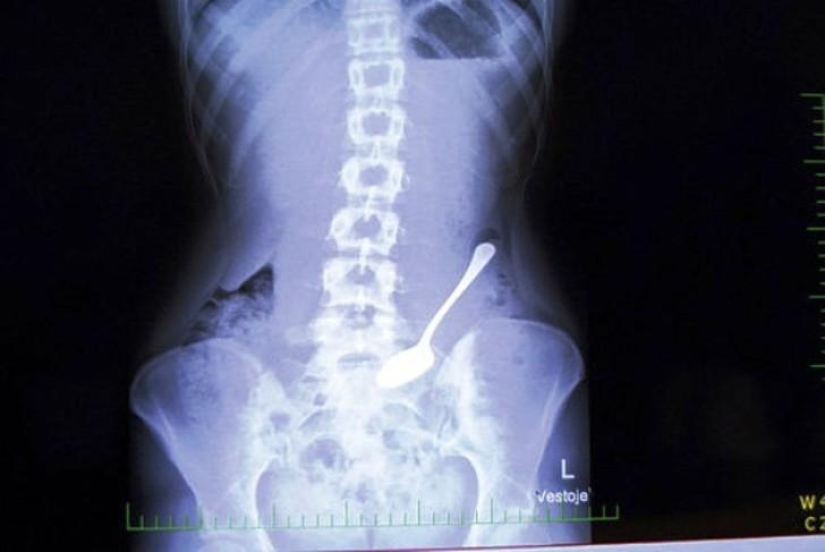

Cuchara.